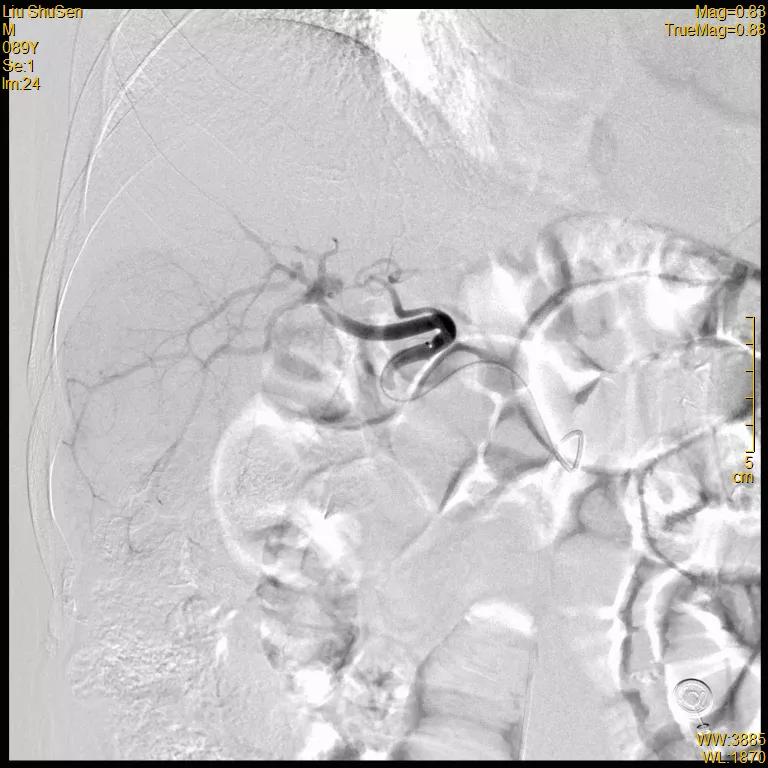

治疗经过:2020-12-18 行TACE术

腹腔干造影

肝固有动脉造影

可见肝右叶明确肿瘤染色

超选至肝右动脉分支1造影+栓塞

栓塞材料:表柔比星60mg+载药

微球;明胶海绵

文章图片

超选至肝右动脉分支2造影+栓塞

微球、碘油;明胶海绵

复查造影:原肿瘤染色不复显影